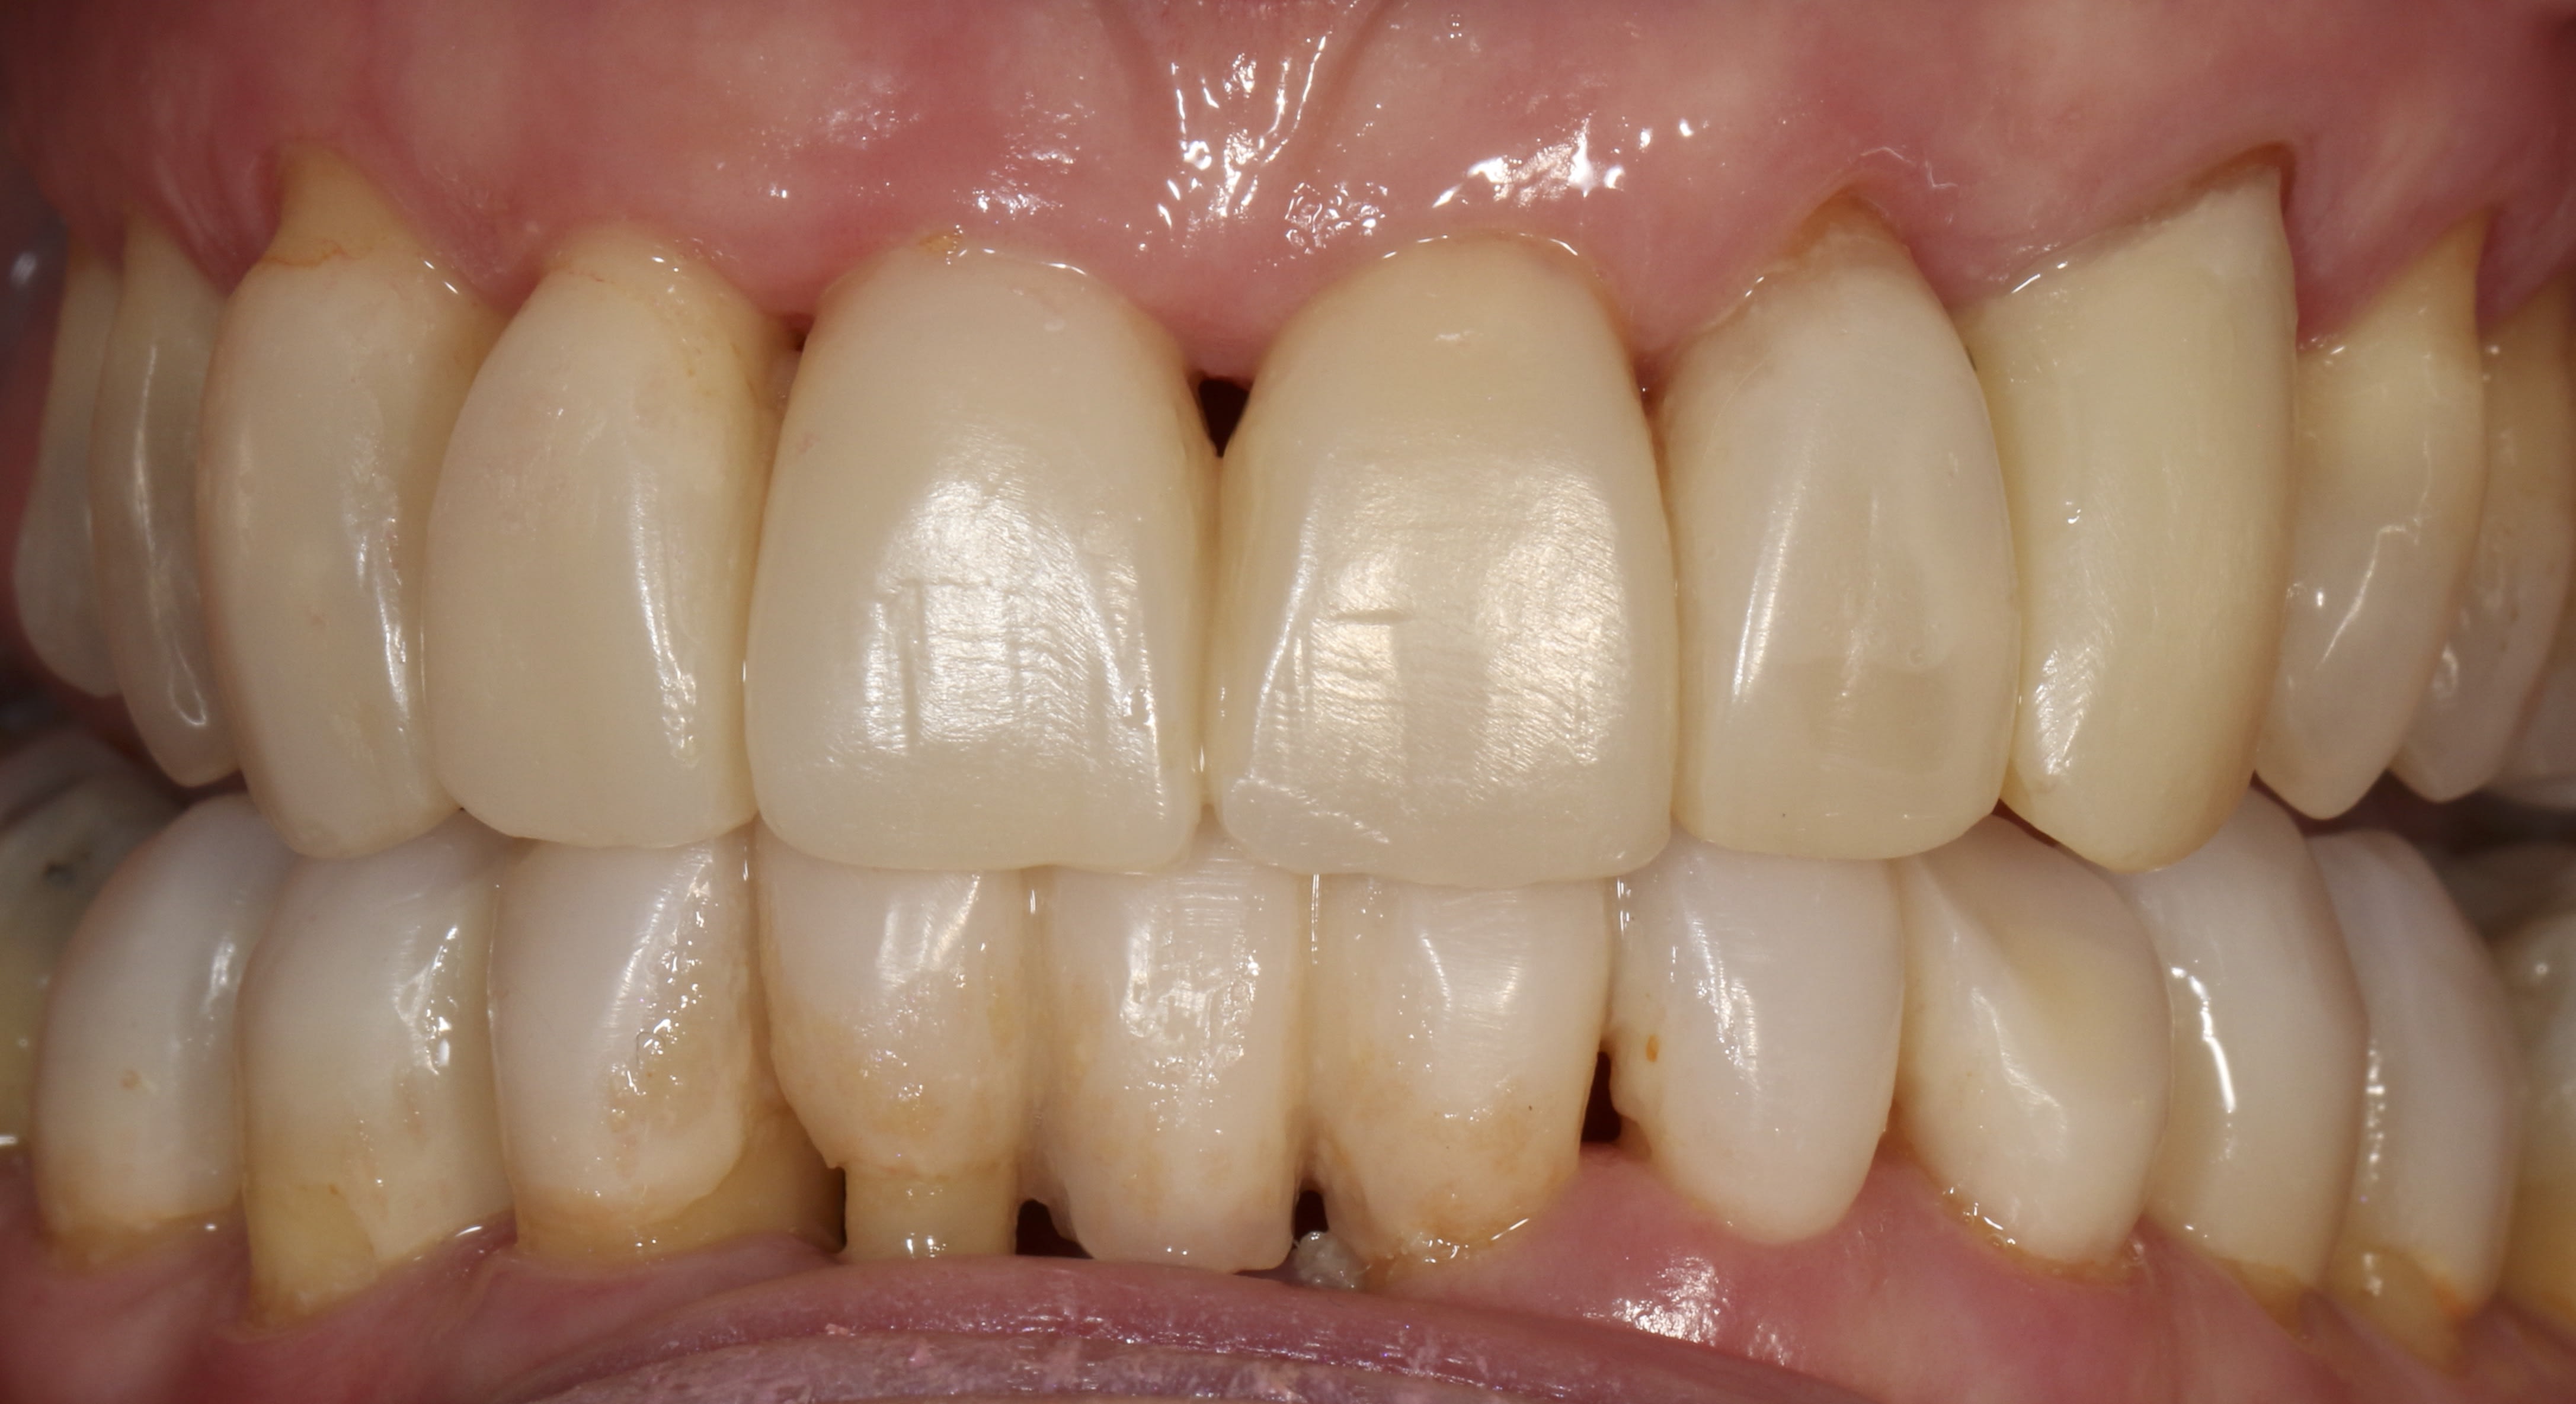

Un p'tit dernier pour la route, avec un visuel à 6 mois

C'est vrai que ça se salit à donf c'te saloperie, bon c'est vrai aussi qu'un p'tit polissage de 15 minutes suffit à leur redonner de l'éclat.....mais chut faut pas le dire, faudrait pas frustrer le gamin.

Tout cela est parfaitement splendide.

Comme j'aime ergoter, je te dirais que des cerams auraient eu une meilleure influence sur la paro du dernier, et auraient peut-être mis moins de temps à réaliser finalement, mais cela n'enlève rien à la maîtrise technique.